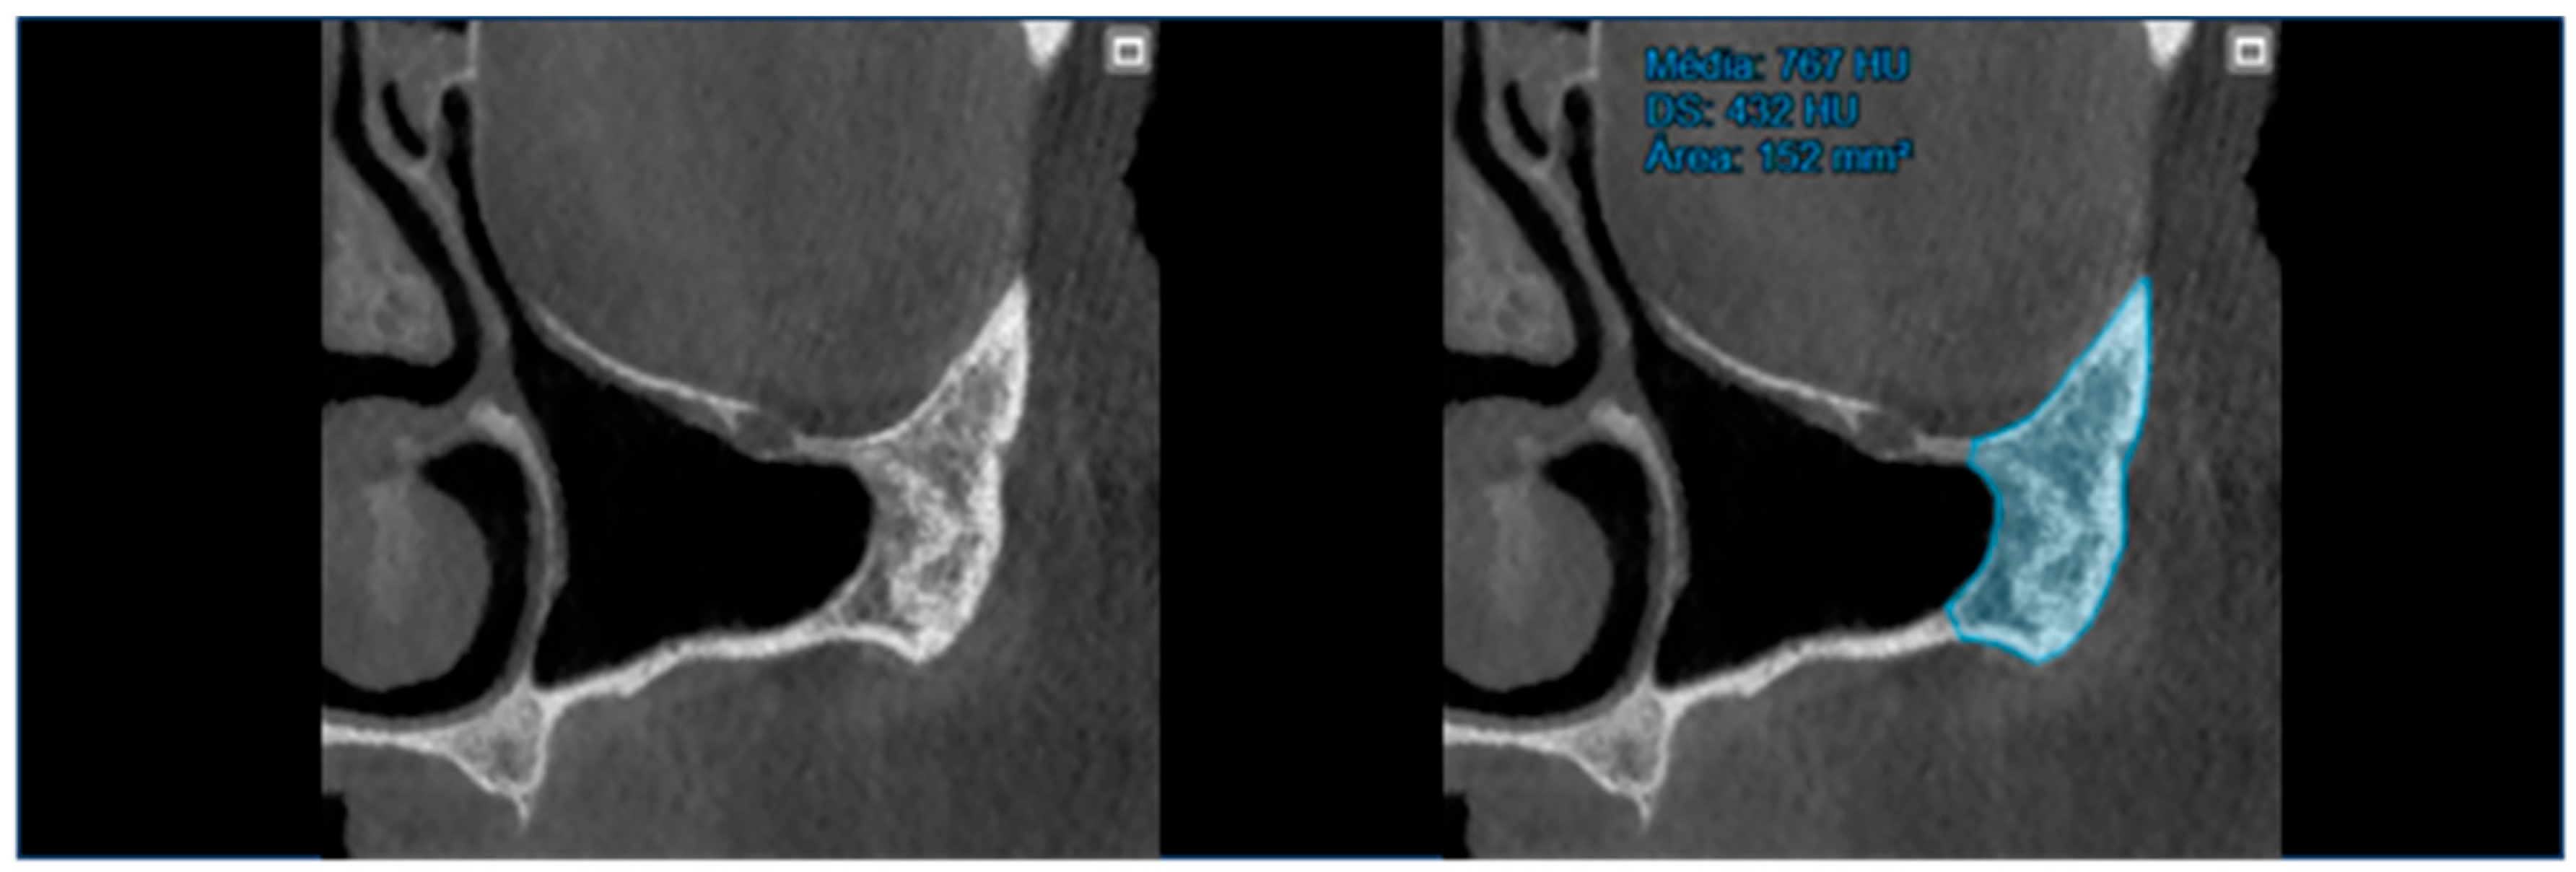

- At T0 (preoperative), the area and bone density of the zygomatic bone were recorded (Figure 1).

| Zygomatic Bone Area (1st Quadrant) (mm2) Mean ± SD, Newtons | T0: 205.96 ± 63.54; T1: 205.96 ± 63.54; T2: 205.96 ± 63.54. |

| Zygomatic Bone Area (2nd Quadrant) (mm2) Mean ± SD, Newtons | T0: 204.18 ± 64.91; T1: 204.18 ± 64.91; T2: 204.18 ± 64.91. |

| Zygomatic Bone Density (1st Quadrant) (HU) Mean ± SD, Newtons | T0: 1077.23 ± 264.90; T1: 2642.06 ± 550.33; T2: 2853.04 ± 530.26. |

| Zygomatic Bone Density (2nd Quadrant) (HU) Mean ± SD, Newtons | T0: 1030.46 ± 314.13; T1: 2457.86 ± 561.85; T2: 2696.60 ± 583.29. |